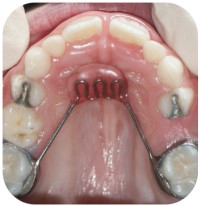

LİNGUAL ARK(lower lingual holding arch (LLHA)): LIngual ark (LLHA) yer koruyan bir apareydir. Alt birinci azı dişlerinize alt dişlerinizin iç tarafı boyunca uzanan bir tel ile bağlanan iki metal banttan oluşur. Bu cihazın amacı alt azı dişlerinizin hareket etmesini önlemektir.